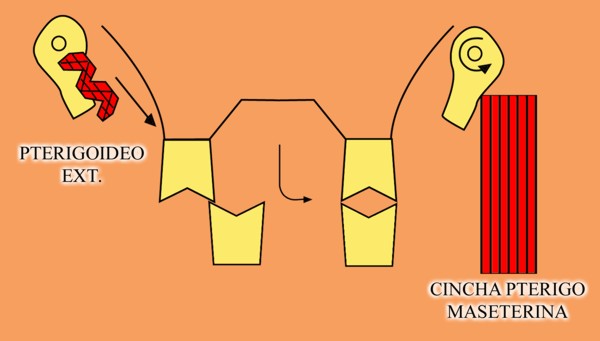

En un esquema de lateralidades a la izquierda, observamos que el Fulcrum de la misma lo encontramos en el cóndilo izquierdo, Cóndilo de Trabajo, la Potencia se encuentra en la fuerza generada por el Pterigoidéo Ext. del lado derecho, Cóndilo de No Trabajo, y la resistencia se dispone, en el caso de una FUNCIÓN DE GRUPO, en las Crestas Triangulares Internas de la tabla premolar-molar superior, que rozan contra las Crestas Centrales antagonistas ,correspondientes al inferior.

Por lo tanto, el Brazo de Potencia se establece entre el CnT(POTENCIA),y el CT(Fulcrum), mientras que los Brazos de Resistencia de las distintas piezas que intervienen en la Función de Grupo, se encuentran entre estas piezas y el CT(Fulcrum).

Como podemos ver en el esquema, estos son menores que el Brazo de Potencia y por lo tanto la fuerza generada por el mismo, producirá mayor deterioro , pues la palanca no está equilibrada:

EL BRAZO DE POTENCIA ES MAYOR QUE EL DE RESISTENCIA (Fig.6)

Sabemos que la fuerza desarrollada por el Pterigoideo Int. y el Masetero, músculos elevadores por excelencia, manifiestan durante el acto masticatorio su máxima expresión(LT), por lo tanto es evidente que dichas fuerzas soportadas fuera del eje axial de la pieza ,determinan grandes daños para las estructuras de soporte.